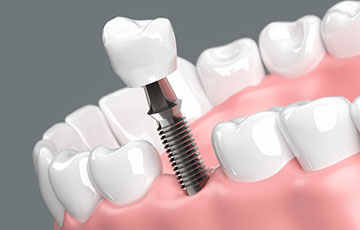

インプラント

- 外科手術を伴う治療である

- オールオン4はインプラント手術を行う治療法のため、全身状態によっては適応が難しい場合があります。重度の持病がある方などは慎重な判断が必要です。治療前にはCT検査や血液検査などを実施し、安全性を確認したうえで適応の可否を判断します。